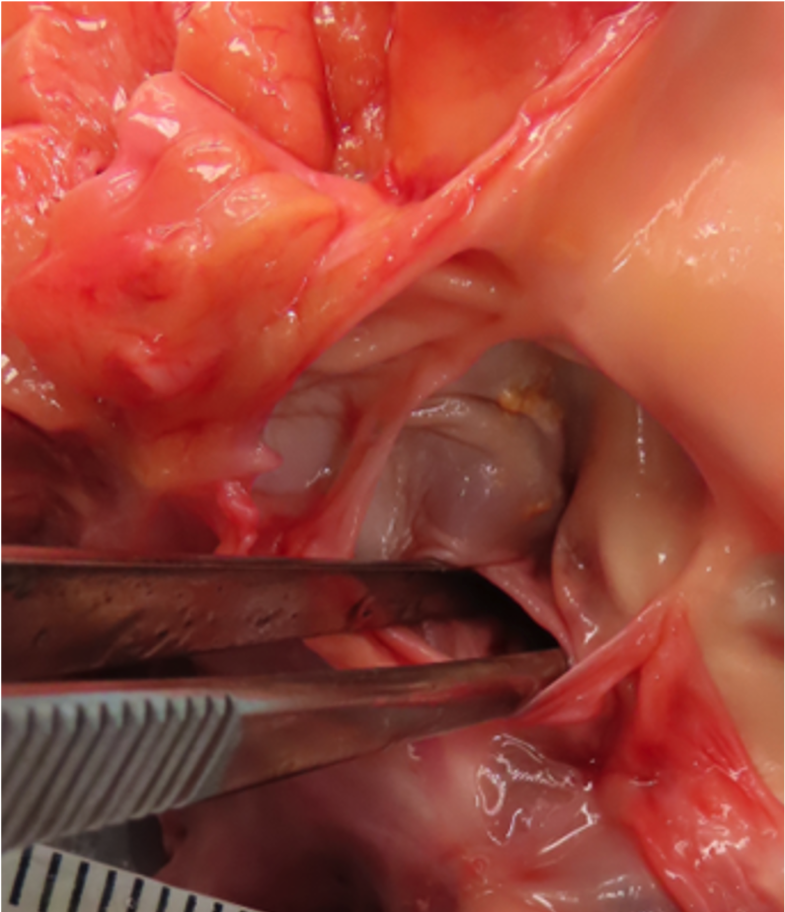

A 24-year-old man was dropped off at home from work around 1800 hours and later found unresponsive on the front porch at approximately 2300 hours by his roommate when he arrived home. The decedent was found supine with vomit next to him. EMS pronounced him dead on scene. Rigor mortis was present in his legs. He was transported to the Medical Examiner’s office for examination. No medical history was available at the time of examination.

Postmortem CT demonstrated cardiomegaly (560 g at autopsy) and no fractures or intracranial hemorrhages. Autopsy images (A-C) are shown.

Which of the following would be the most likely associated with this autopsy finding?